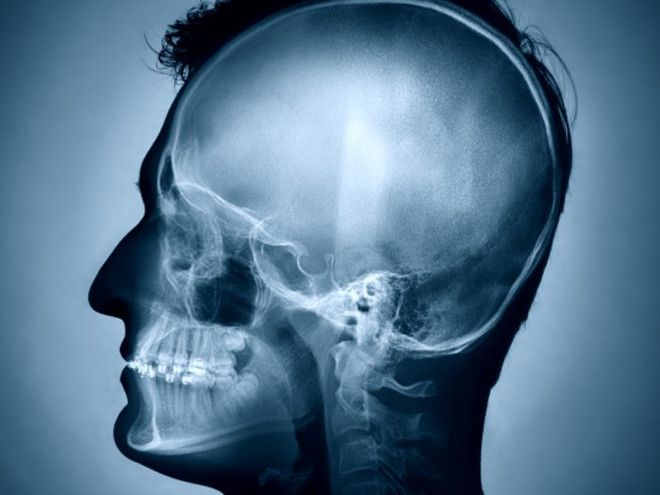

Мы используем только 10 процентов мозга

Большинство людей использует только около 10 процентов от их мозга, и только исключительные гении используют более этого объема. Есть части мозга, которые могут быть никогда не использованы любым человеком. По мнению профессиональных ученых-физиологов, мы на самом деле используем почти все наши мозговые ресурсы и там просто нет ни одного сектора, который бы оставался в покое в течение дня. Некоторые исследователи признают, что действительно, около 10 процентов клеток мозга остаются активными в любой момент времени, даже в состоянии глубокого сна.